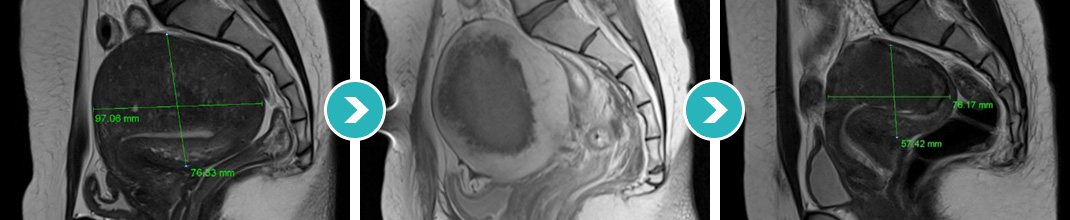

9cm 크기 자궁전벽의 자궁선근증 하이푸 치료후 80~90%이상 치료, 6개월 추적관찰